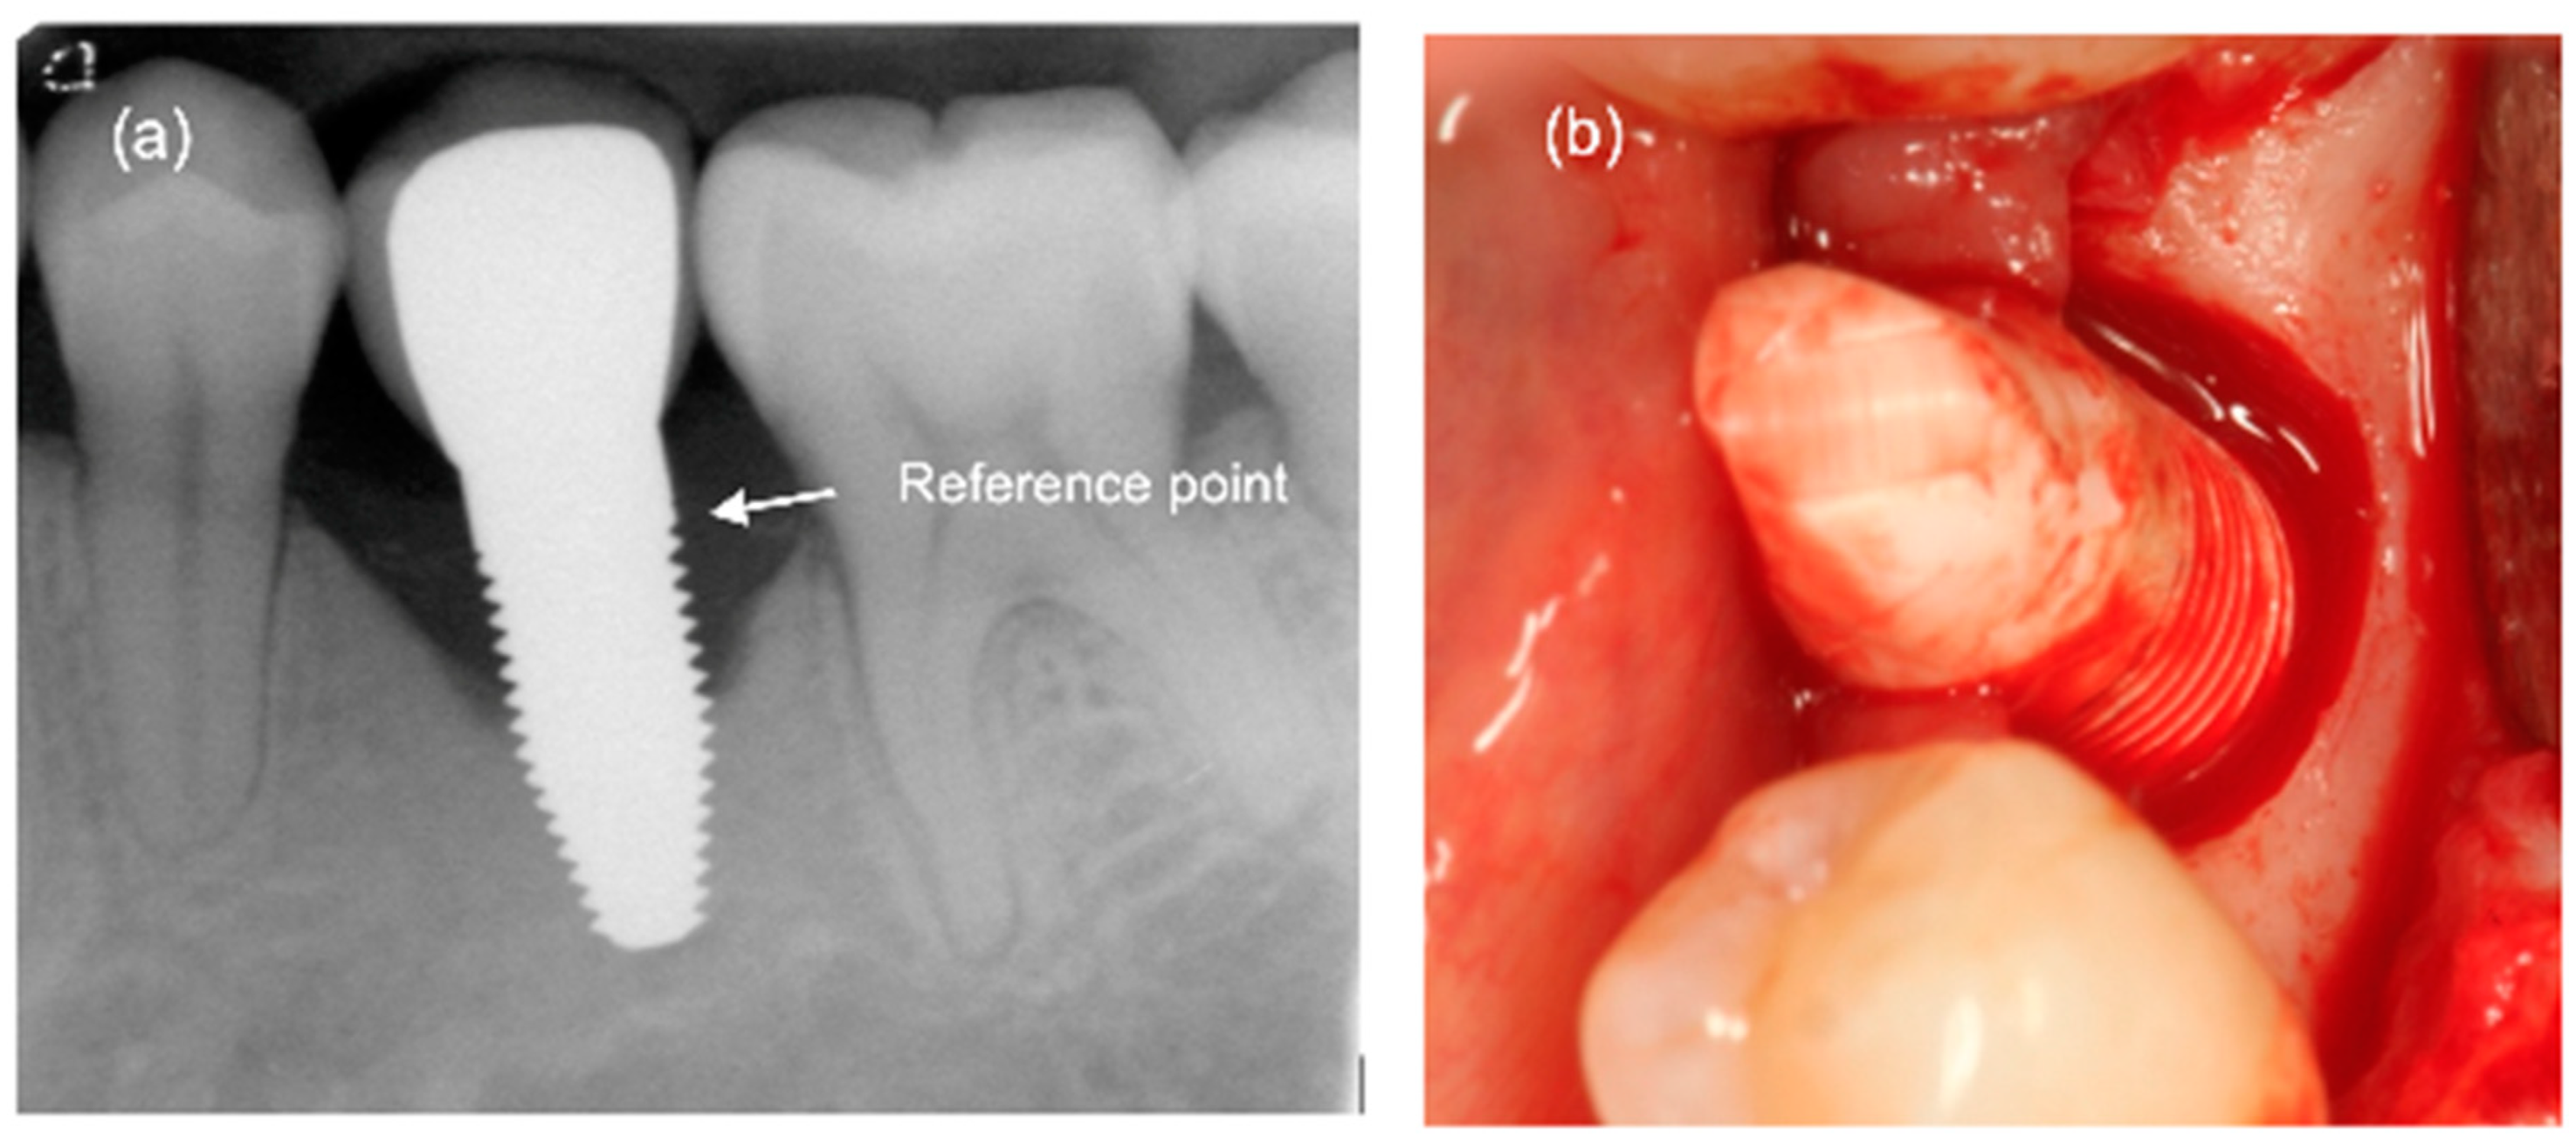

Appendix B. Exemplary Photographs and Radiographs from a Patient at Different Examination Time Points and a More Negative Outcome